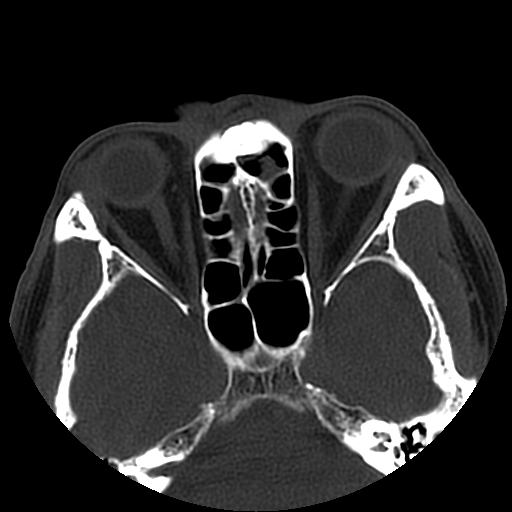

以下是引用liaoqiang在2008-7-16 21:15:00的发言:[br]右侧鼻骨骨折

以下是引用zxd95在2008-7-16 21:39:00的发言:[br]右侧上颌骨额突骨折。[br][br][br][br]